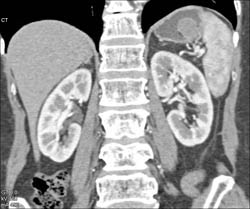

Diagnosis

GIST Tumor